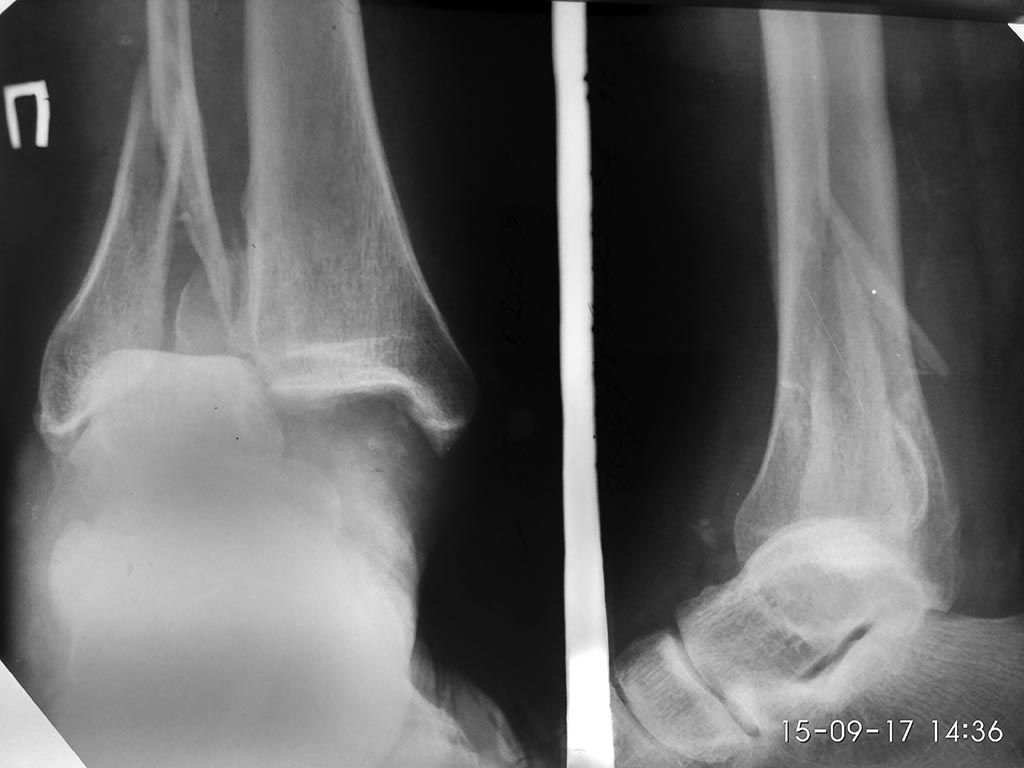

[Ortho] Осложненный перелом лодыжек - подскажите тактику

Артерии проходимы ,глубокие вены  - тромбоз ,возвратный кровоток за счет

поверхностных, эластичная компрессия противопоказана.

Имя     : IMG_20170915_143700_HDR.jpg